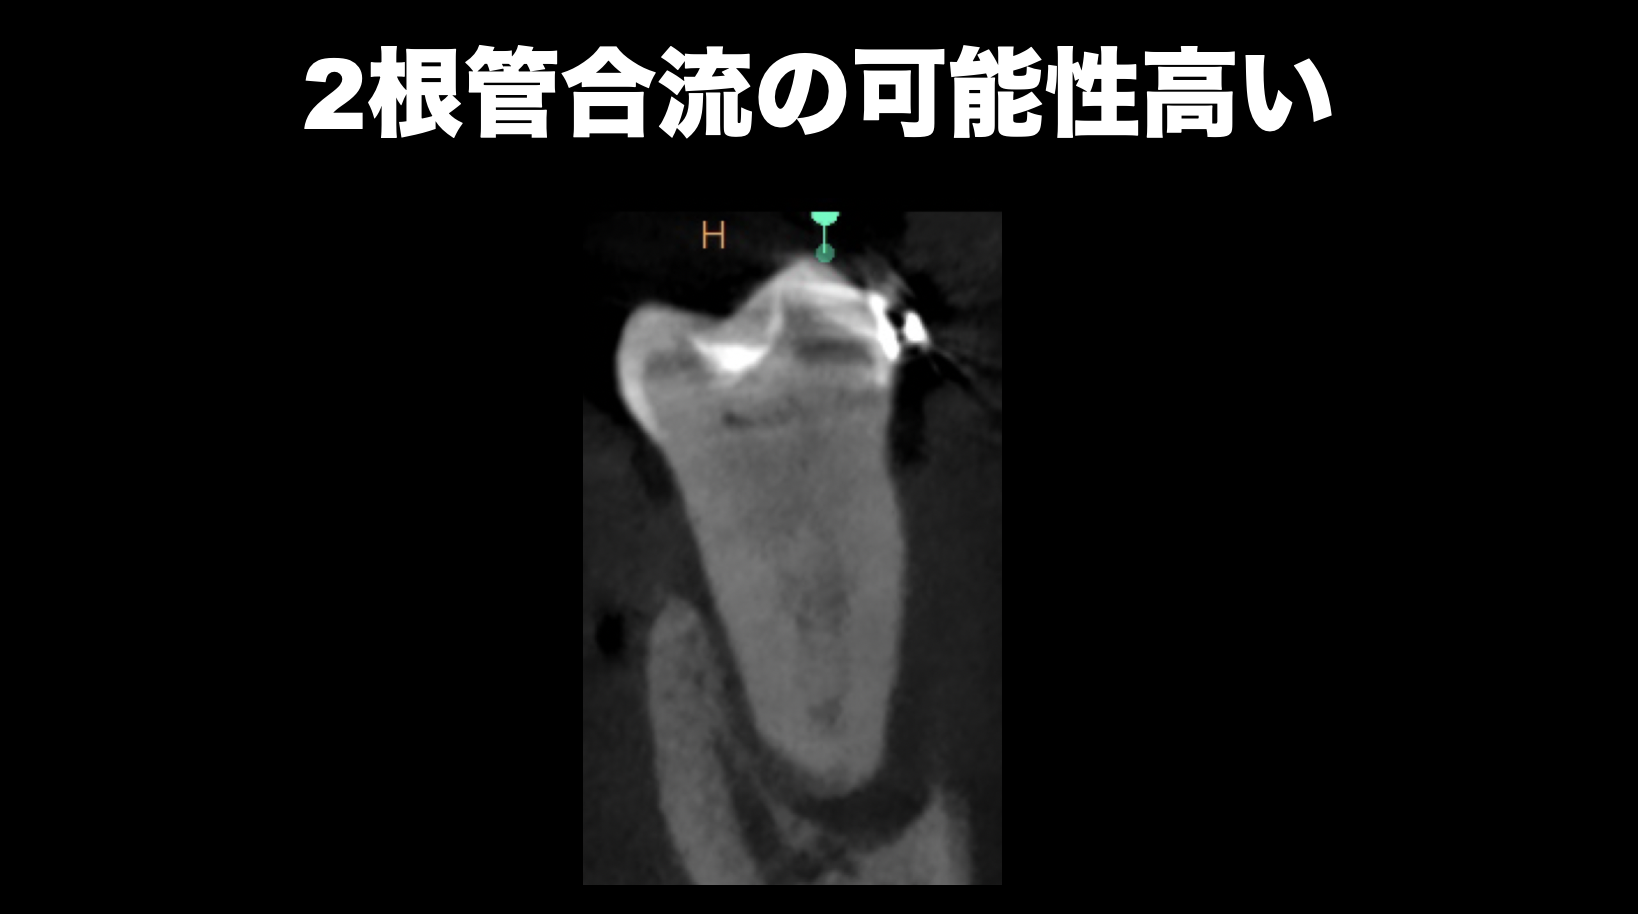

そして最後にケースを提示した。